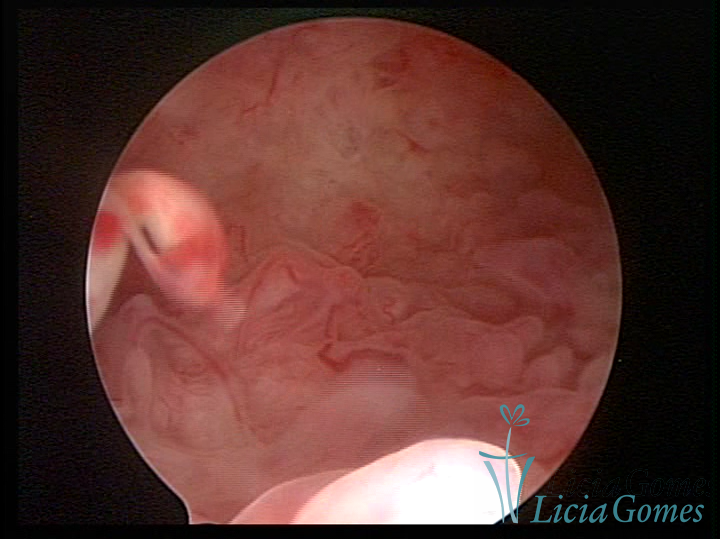

A histeroscopia permite analisar as características da superfície endometrial, não podendo avaliar a profundidade ou o grau de invasão miometrial.

Mas poderá verificar se as lesões são do tipo: focal; regional ou difusa